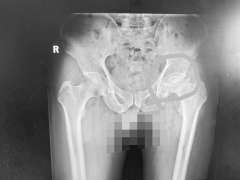

确诊  原来是股骨头坏死

“之前的骨科医生应该是受到了王女士的诱导,因为她见到医生就说自己是腰脱,导致医生忽视了其他骨科疾病的诊断。腿变短了,可能是股骨头出了问题。”蔡振存表示。通过股骨头部位的影像检测,王女士被确诊为股骨头坏死。通过股骨头置换手术,王女士的病得到了彻底解决。

腰椎滑脱是指相邻两节椎体发生错位,当刺激周围神经根时会引起腰部剧烈疼痛。股骨头坏死会导致髋关节内压增高,引发剧烈疼痛。腰脱带着的大腿疼反射区主要是大腿后外侧,并且往往都连带小腿外侧,甚至放射到足部。股骨头坏死的疼痛一般在大腿内侧以及膝关节的前内侧。也就是说,一个是前内,一个是后外,并且股骨头坏死,一般不会带着小腿和脚疼。